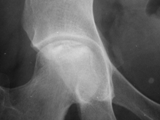

AVN-femur

AVN-femur